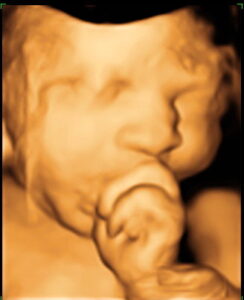

3D/4D Technology

Ultrasounds are an essential tool to visualize the fetus and uterus. Traditional 2D ultrasound technology has been utilized for over 30 years and most pregnant patients have at least 2 ultrasounds during their pregnancy. Recent advances in imagery have resulted in the introduction of three and four-dimensional ultrasound, giving obstetricians who suspect a fetal abnormality a specific surface rendering of the fetus. Dr. Keith Lescale has completed thousands of scans and has been using this innovative equipment since 2002.

Physicians refer patients to Dr. Lescale for 3D/4D ultrasound to better detect fetal abnormalities and structural problems, such as cleft lip, spinal abnormalities, and cardiac deformities. According to Dr. Lescale there are a few limitations to sufficient visualization of fetal anatomy with 3D/4D technology. There will be difficulty visualizing structures or the baby’s face if there is inadequate amniotic fluid surrounding the fetus, or if the fetus has its face in the posterior position in the uterus. The 3D/4D technology is paid for by most major insurances when medically indicated.